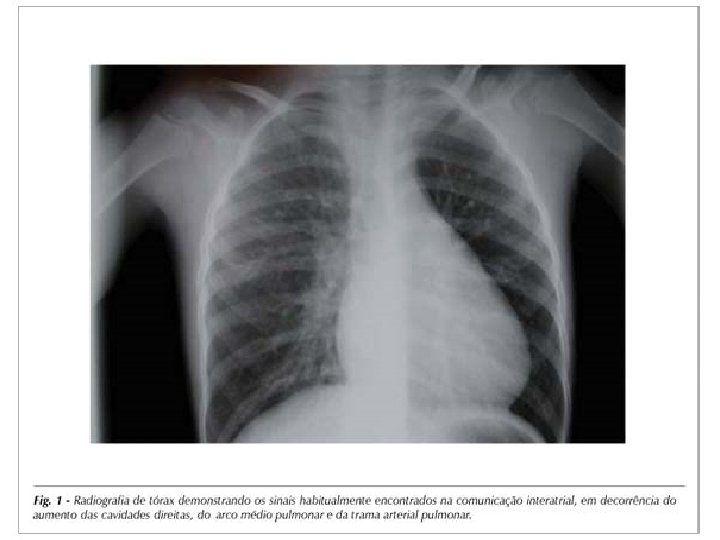

RADIOGRAFIA DE TÓRAX • CIA tipo ostium secundum e grande desvio esquerda direita – área cardíaca (AD e VD) e vascularidade pulmonar – Tronco pulmonar dilatado • CIA tipo seio venoso – VCS, dilatação ampular – Elevação do pedículo vascular pulmonar direito